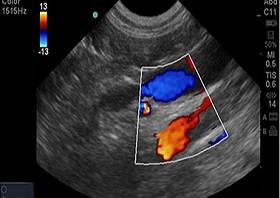

COLOUR DOPPLER USG

A Doppler ultrasound is a test that uses high-frequency sound waves to measure the amount of blood flow through your arteries and veins, usually those that supply blood to your arms and legs.

Vascular flow studies, also known as blood flow studies, can detect abnormal flow within an artery or blood vessel. This can help to diagnose and treat a variety of conditions, including blood clots and poor circulation. A Doppler ultrasound can be used as part of a blood flow study.